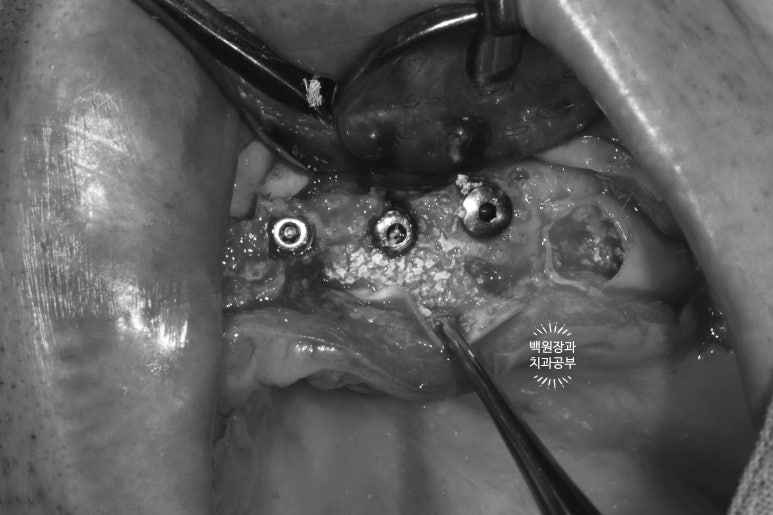

약 2주가 지난 시점에, 아래턱 임플란트 수술도 진행!

아래턱 임플란트도 오스템 임플란트의 네비게이션 임플란트 시스템인,

오스템 원가이드를 이용한 가이드 서저리로 시행하였습니다. 보시면 여섯개의 임플란트 수술이 예정된 것을 확인할 수 있죠.

수술 하기 전 다시 봐도 정말.. 너무너무 얇은 잇몸뼈를 보실 수 있습니다.

칼 ridge라고도 부르는데... 손이 베일 것 같이 얇은 뼈 높이..

이런 경우 얇은 잇몸뼈는 일부 삭제 후 두꺼운 뼈 부위에 뼈이식을 하면서 임플란트를 위치시키게 됩니다.

앞쪽에 식립되었던 4개의 임플란트는 역시나.. 얇은 잇몸뼈 밖으로 일부를 드러내고 있는 모습을 볼 수 있었구요..

이번에도 역시 덴티움 社의 합성골인 osteon III와 주변에서 채득했던 자가골을 이용하여 충분한 뼈이식을 해드렸습니다. 비용이 다소 추가되지만, 성공적인 뼈이식을 하기 위해서 같은 회사의 '흡수성 콜라겐 차폐막'은 반드시 사용되어야 합니다.

이것이 GBR (guided bone regeneration)의 기본 원리입니다.

열심히 예쁘게 꿰매드리고 나서 .. (생각보다 너무 깔끔하잖아..?)

보면 뼈이식이 많이 된 것 같지 않나요?

상당히 볼쪽으로 뚱뚱해진 잇몸뼈를 보실 수 있을겁니다.

유독 앞니의 뼈가 얇아 더 많이 뼈이식을 했던 기억이 납니다.